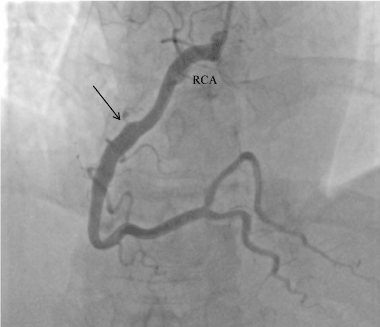

We present the case of a 40-years-old male, irregularly treated for arterial hypertension, with history of nicotinism, with no burden of family history of cardiovascular problems, admitted to the Cardiology Clinic because of STEMI of the anterior wall, in the 6th hour after onset of pain. The patient for the first time in his life experienced a typical pain in the chest, lasting for two hours, with accompanying vegetative symptoms: anxiety, weakness and increased perspiration. At admission the patient was in overall relatively good condition, with sufficient circulation and respiration, with increased blood pressure of 160/100 mmHg, SO2 98%; in ECG - steady sinus rhythm 74 bpm, QS complexes in V1-V4, with ST elevation by 2 mm in V2-V4. Markers of myocardial necrosis were increased: TnT 2.17ng/mL (normal range up to 0.014 ng/mL), CKMB 138 ng/dL (normal range up to 4.87 ng/dL). Coronarography performed in urgent mode demonstrated obstructed left anterior descending artery (LAD) and aneurysm of its proximal segment (Figure 1). In the right coronary artery (RCA) an ectasia was observed, involving its third segment (Figure 2). Restoration of patency of LAD was attempted, but was unsuccessful. Conservative treatment of acute coronary syndrome was implemented, according to the typical scheme. Considering long time passed since the onset of pain, a fibrinolytic treatment was not used. Control echo of the heart performed at rest demonstrated apical hypokinesia of the inferior wall, anterior wall and interventricular septum; the global ejection fraction was 52%. On the 8th day of hospitalisation the patient had exercise echocardiography performed, demonstrating improved contractility of hypokinetic segments of the left ventricle. The patient was qualified for aortic-coronary bypass grafting of the closed LAD, using the MIDCAB method.

Figure 1. Left coronary artery ( LCA). The aneurysm can be seen in the proximal segment of left anterior descending artery (LAD); the distal part is occluded. ( the arrow shows the amputation of LAD). Cx – Circumflex artery, MA – left marginal artery, Dx- 1st left diagonal artery